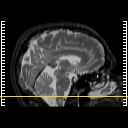

Click on sagittal image to select slice. Click on thin tickmark to change timepoint, or thick tickmark for overlay.